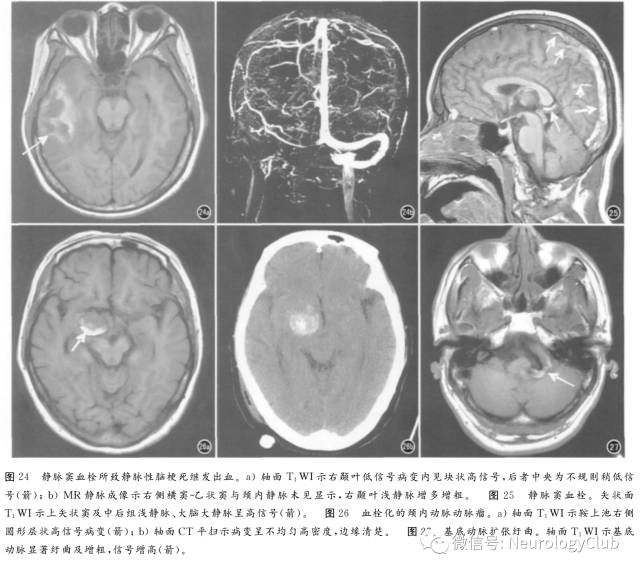

脑梗死的短T1信号主要见于亚急性期,原因包括出血与皮质层状坏死,病理学基础为脱氧血红蛋白、高铁血红蛋白、铁、钙盐及其他顺磁性物质沉积。继发于抗凝治疗或再灌注所致的出血,称为出血性转化(图22),临床病例发生率高达43%,病理学发现率更高。T1WI高信号自发病第2天至2个月末均可出现。皮质层状坏死呈皮质线状或脑回状高信号(图23),见于2周后,1-2个月时最明显,可持续至第18个月,T2*WI及SWI序列研究表明并非出血,病理学上铁染色阴性,镜下显示为坏死碎屑中的蛋白变性,少数病例SWI序列上斑点状低信号可能代表顺磁性物质如锰与自由基沉积。多灶性出血性梗死提示为栓塞性,见于心内膜炎等。鉴别诊断包括肿瘤出血、静脉性脑梗死。

4. 静脉窦血栓

约40%脑静脉或静脉窦血栓合并出血,血肿本身MRI表现无特殊性,同时显示的脑静脉或静脉窦T1WI高信号(约97%)可提示诊断(图24、25)。

5. 动脉瘤

颅内动脉瘤及其出血均可造成短T1信号,约30%动脉瘤破裂造成脑内血肿,表现与自发性脑出血相同。动脉瘤本身短T1信号原因包括慢血流造成的流动相关增强与血栓形成,超过25mm的巨大动脉瘤至少管腔部分血栓化,呈特征性的层状或向心性,不同期龄血栓为层状T1WI中高信号(图26),通畅部分则为流空信号。大型动脉瘤血流复杂、动脉纡曲、动脉瘤样扩张(图27)、流速快及涡流明显,信号更加混杂,需注意的是常规SE序列难以鉴别慢血流与腔内血栓,此时需行流动敏感序列扫描。